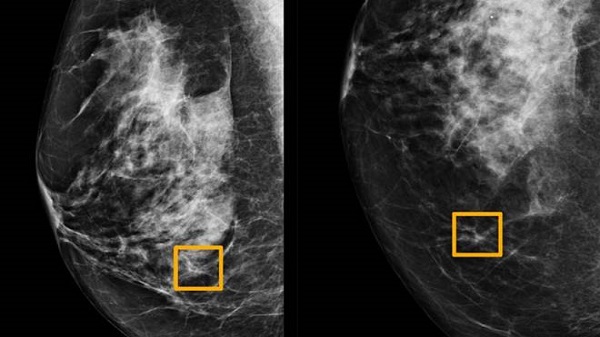

ലണ്ടനിലെ ഇംപീരിയൽ കോളജിലെയും ബ്രിട്ടനിലെ നാഷണൽ ഹെൽത്ത് സർവീസിലെയും ഗവേഷകർ ഉൾപ്പെട്ട സംഘം പതിനായിരക്കണക്കിന് മാമോഗ്രാമുകളിൽ സ്തനാർബുദം കണ്ടെത്തുന്നതിനുള്ള സംവിധാനത്തിന് പരിശീലനം നൽകി. ബ്രിട്ടനിലെ 25,856 മാമോഗ്രാമുകളിൽ നിന്നും അമേരിക്കയിൽ നിന്നുള്ള 3,097 ൽ നിന്നുമുള്ള യഥാർത്ഥ ഫലങ്ങളുമായി അവർ അതിന്റെ പ്രവചനങ്ങളെ താരതമ്യം ചെയ്തു. വിദഗ്ദ്ധരായ റേഡിയോളജിസ്റ്റുകൾക്ക് സമാനമായ അളവിലുള്ള ക്യാൻസറിനെ എ.ഐ സിസ്റ്റത്തിന് തിരിച്ചറിയാൻ കഴിയുമെന്ന് പഠനം തെളിയിച്ചു, അതേസമയം തെറ്റായ പോസിറ്റീവ് ഫലങ്ങളുടെ എണ്ണം യു.എസ് അധിഷ്ഠിത ഗ്രൂപ്പിൽ 5.7 ശതമാനവും ബ്രിട്ടീഷ് അധിഷ്ഠിത ഗ്രൂപ്പിൽ 1.2 ശതമാനവും കുറയ്ക്കുന്നു.

തെറ്റായ നിർദേശങ്ങളുടെ എണ്ണവും ഇത് വെട്ടിക്കുറച്ചു, അവിടെ ടെസ്റ്റുകളെ സാധാരണ എന്ന് തെറ്റായി തരംതിരിക്കുന്നു. യു.എസ് ഗ്രൂപ്പിൽ 9.4%, ബ്രിട്ടീഷ് ഗ്രൂപ്പിൽ 2.7% എന്നിങ്ങനെയാണ്. ഈ വ്യത്യാസങ്ങൾ മാമോഗ്രാമുകൾ വായിക്കുന്ന രീതികളെ പ്രതിഫലിപ്പിക്കുന്നു. അമേരിക്കൻ ഐക്യനാടുകളിൽ, ഒരു റേഡിയോളജിസ്റ്റ് മാത്രമാണ് ഫലങ്ങൾ വായിക്കുന്നത്, കൂടാതെ ഓരോ ഒന്ന് മുതൽ രണ്ട് വർഷം കൂടുമ്പോഴും പരിശോധനകൾ നടത്തുന്നു. ബ്രിട്ടനിൽ, ഓരോ മൂന്നു വർഷത്തിലും പരിശോധനകൾ നടത്തുന്നു, ഓരോന്നും രണ്ട് റേഡിയോളജിസ്റ്റുകൾ വീതം നടത്തുന്നു. അവർ വിയോജിക്കുമ്പോൾ, മൂന്നിലൊന്ന് ആലോചിക്കുകായും ചെയ്യുന്നു.